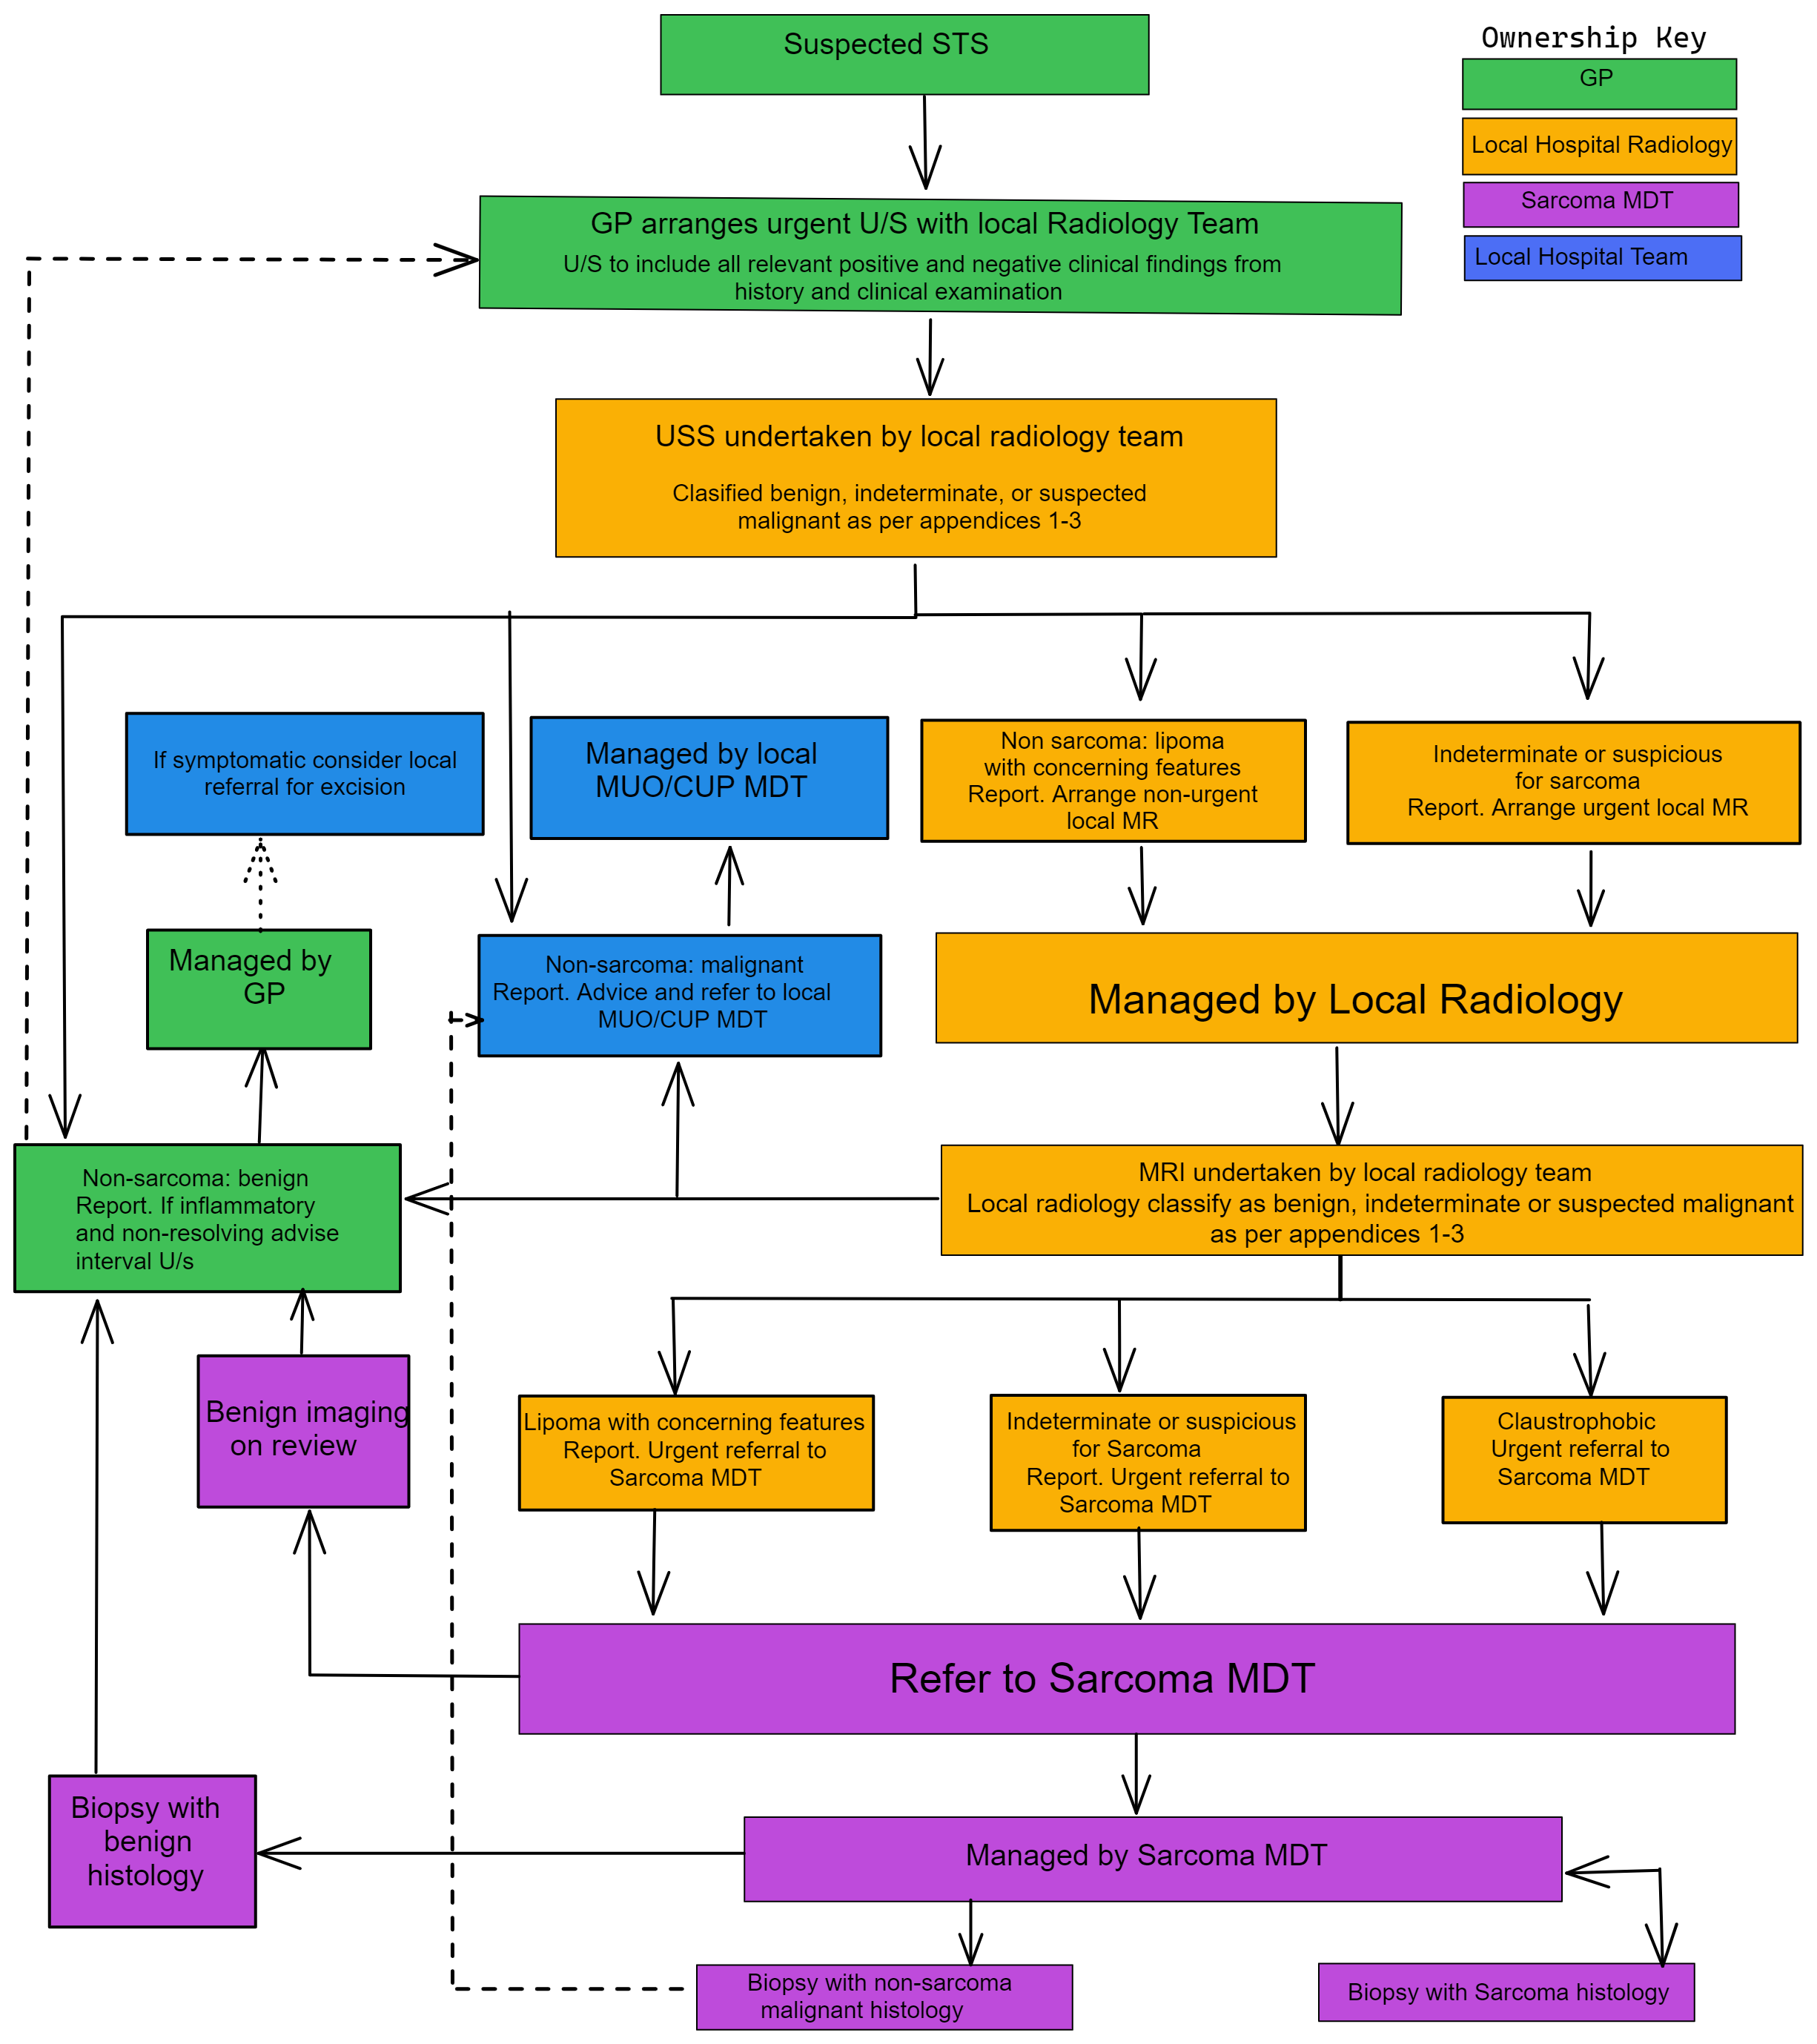

https://yorkshireimaging.nhs.uk/images/sarcoma-2-.png

Lipoma Removal Guidelines Infoupdate